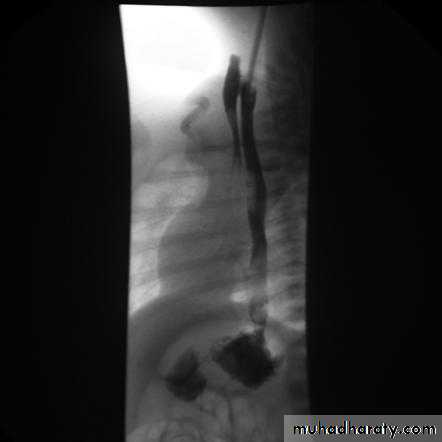

Stricture

Benign vs. malignant Causes Specific locationContrast study EUS CT